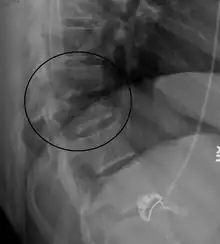

A flexion-distraction fracture of T10 and fracture of T9 due to a seatbelt during an MVC.

On plain X-ray, a Chance fracture may be suspected if two spinous processes are excessively far apart.[10]

A CT scan of the chest, abdomen, and pelvis is recommended as part of the diagnostic work-up to detect any potential abdominal injuries.[5][10] MRI may also be useful.[10] The fracture is often unstable.[1]